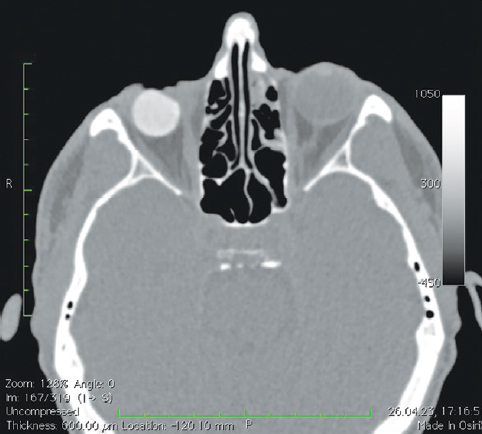

Рис. 7. Пациентка, 32 года. 3 года после операции с имплантацией эндопротеза с изменённой геометрией. МСКТ-исследование глазниц

Fig. 7. Patient, 32 y. o. 3 years after surgery with implantation of an endoprosthesis with modified geometry. MSCT of the socket

При анализе рентгенологических изображений после выполнения МСКТ-диагностики у всех обследованных пациентов по описанному ранее алгоритму [16] нами было выявлено изменение размеров и геометрии орбитальных сфер в виде «срезанной» части (рис. 8). Параметры изменённой части, как и размеры самих имплантатов, были различны (табл. 1–3). Исходные параметры (диаметры) орбитальных сфер — 18, 19 и 20 мм. При компьютерно-томографическом исследовании на полученных изображениях мы анализировали размеры имплантированных материалов, определяя объём вкладышей через радиус и высоту срезанной части по формуле: V = 1/3πh2(3r – h), где π — константа, равная 3,14; r — радиус шара; h — высота шарового сегмента имплантата.

В мягких тканях вокруг изменённых имплантированных сфер нами выявлены уплотнения, без признаков кальцинации и деструкции стенок орбиты (рис. 7, 8). Кроме того, у одной пациентки было отмечено не только изменение геометрии сферы в виде срезанной части (рис. 10, а), но и наличие множества фрагментов полимерного материала идентичной рентгенологической плотности. Эти фрагменты имплантата находились за задним полюсом полимерного вкладыша в мягких тканях до вершины орбиты (рис. 10, b).